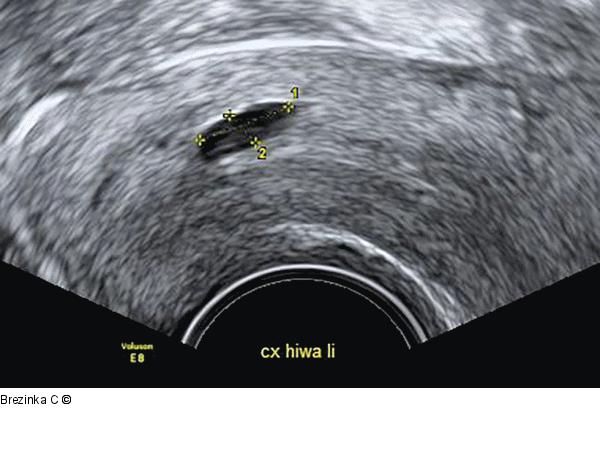

Abbildung 6: Ovulum Nabothii Ovulum Nabothii an der Zervixhinterwand. |